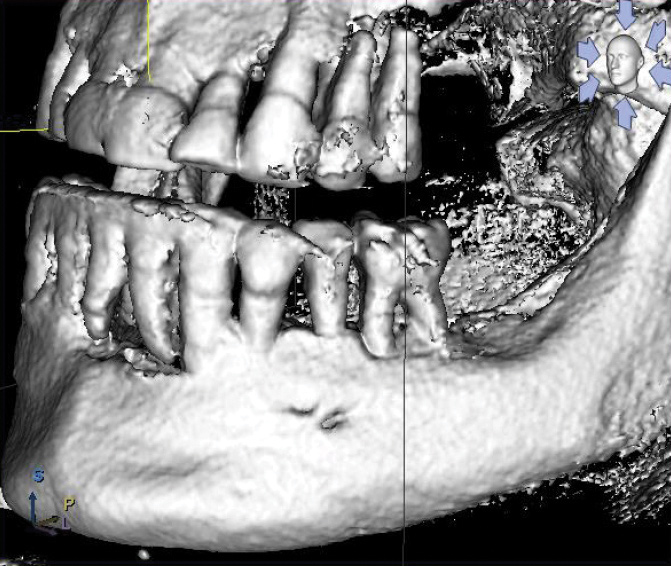

Accessory Mental Foramina

The prevalence of accessory mental foramina is well documented in dental literature with findings from 2.7% to 13% (Figure 11).30-32 Accessory mental foramina pose a particular obstacle for All-on-4–style treatment because the mental foramen is the landmark used to determine the posterior limits of tilted implant placement (Figure 12).9 The presence of accessory mental foramina often requires more mesial placement of dental implants, thus limiting the anterior-posterior spread of the All-on-4–style prosthesis. Furthermore, in cases in which accessory mental foramina are located superior to the main mental foramen,30 the amount of bone reduction may be compromised, increasing the risk for prosthetic fracture.25 Presurgical cone-beam computed tomography (CBCT) scans and radiographs for proposed All-on-4–style surgeries should be scrutinized for accessory mental foramina (Figure 13). Notably, dental literature has shown that even with careful evaluation of CBCT scans, it is not possible to identify 100% of accessory mental foramina cases.31 As such, care should be taken during mucogingival flap reflection to search for this anatomic anomaly.

When encountering accessory mental foramina, the author has performed modifications to bone reduction and/or more mesial placement of posterior dental implants; on a few occasions, he has carefully dissected the nerve from the accessory mental foramen and relocated it to a more distal position. To date, the author has had no adverse outcomes in patients, such as permanent or transient anesthesia, paresthesia, hypoesthesia, or dysesthesia, resulting from this technique.

Fig 12. CBCT imaging of accessory mental foramina from Figure 11.

Figure 12

Fig 13. Mental foramen used to determine the posterior extent of tilted dental implant placement in a mandibular All-on-4–style dental implant surgery.

Figure 13